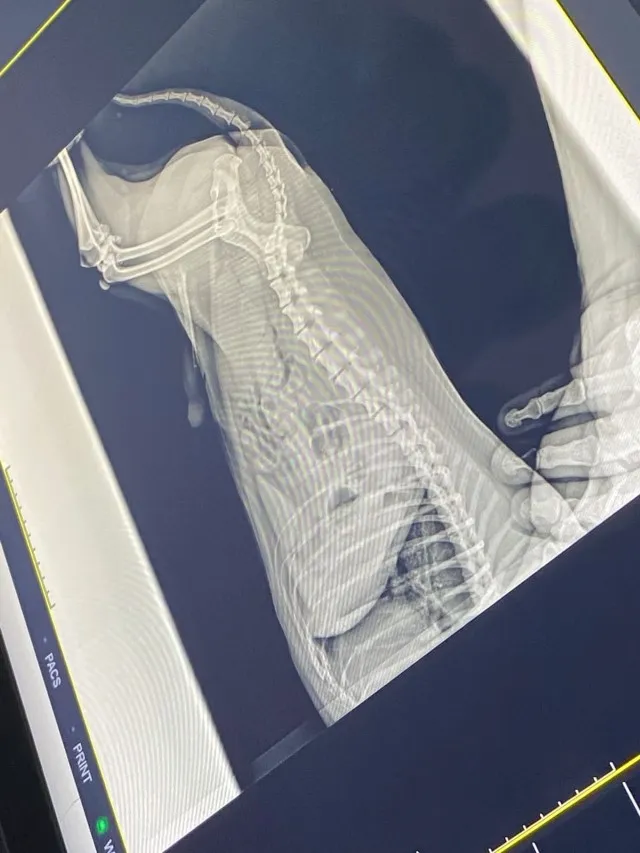

Leandro Magoga trabalha há mais de 6 anos como técnico de raio X de animais de pequeno porte, silvestres e exóticos, e mostrou para as turmas de Medicina Veterinária alguns pontos importantes na hora de fazer a radiografia, como o aparelho que se utiliza. Magoga ainda conversou sobre como fazer a calibragem do aparelho, a colimação (processo de alinhamento das lentes), o tempo de disparo e a quantidade de raios emitidos por diferentes aparelhos.

O professor Erick Villela quis mostrar como esse processo e aprendizado é essencial para a carreira profissional dos estudantes, já que em algumas clínicas é pedido que o veterinário clínico saiba o básico sobre imagem radiográfica e o posicionamento dos animais.

“A conversa com os alunos foi interessante, pois, além de ser essencial para o futuro profissional deles, mostrou como é importante saber o processo de laudar uma imagem e como fazer o pedido de uma radiografia de maneira correta”.